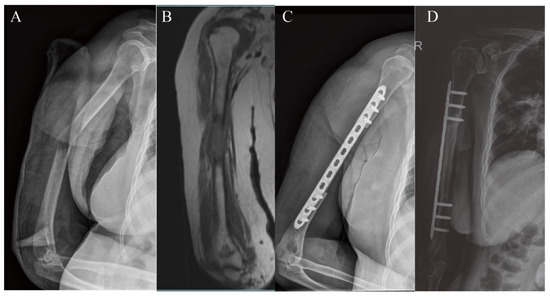

3.1. Upper Extremity Reconstruction Results